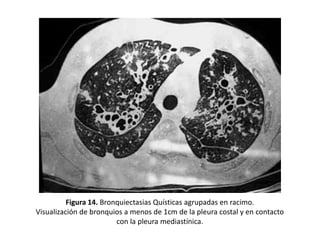

• Visualización de bronquios a menos de 1 cm de

la pleura costal o en contacto con la pleura

mediastínica.

– En pacientes con BQ la dilatación de la luz bronquial,

el engrosamiento de su pared y la fibrosis

peribronquial permiten la visualización de bronquios

en la periferia del pulmón (Figuras 9, 11 y 14)

Figura 14. Bronquiectasias Quísticas agrupadas en racimo.

Visualización de bronquios a menos de 1cm de la pleura costal y en contacto

con la pleura mediastínica.